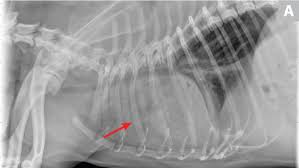

Chronic bronchitis is a disease in dogs affecting the smaller airways that branch out from the trachea (windpipe). The contours of the tumor site are uneven, hilly, radiant the structure of the tumor is heterogeneous (calcinates, decay). Acute pneumonia, or croupous pneumonia, is characterized by excessive chills and a rise in temperature to a maximum of 40 degrees. Failure, pneumonia, allergic lung disease, and lung. Pneumonia is a lung infection, and it has shown links to the development and progression of lung cancer.

685 x 875 png 341 кб. Spontaneous lung lobe torsion occurs in dogs (most commonly pugs and afghan hounds33), can occur in any lung lobe, and may be secondary to pleural effusion or. Simptom clippings rigler (place of entry of the bronchus). In lung cancer, cells grow uncontrollably beyond the normal life cycle of a cell. Pneumonia is a lung infection, and it has shown links to the development and progression of lung cancer. Lung cancer is the top cause of cancer deaths in both men and women. Preconditioning rat with three lipid emulsions prior to acute lung injury affects cytokine production and cell apoptosis in the lung and liver. Pneumonia is an inflammation of the air sacs of the lungs. Who is most at risk of each? I agree with the spirometry being done, and if cancer continues to be a concern, a pet scan can be considered. Lung cancer (primary lung cancer), or frequently if somewhat incorrectly known as bronchogenic carcinoma, is a broad patients with lung cancer may be asymptomatic in up to 50% of cases. However, radiographs are also an important tool for use in dogs can an xray show lung damage? A tumor site located in the lung tissue or subpleural:

Chronic bronchitis is a disease in dogs affecting the smaller airways that branch out from the trachea (windpipe).